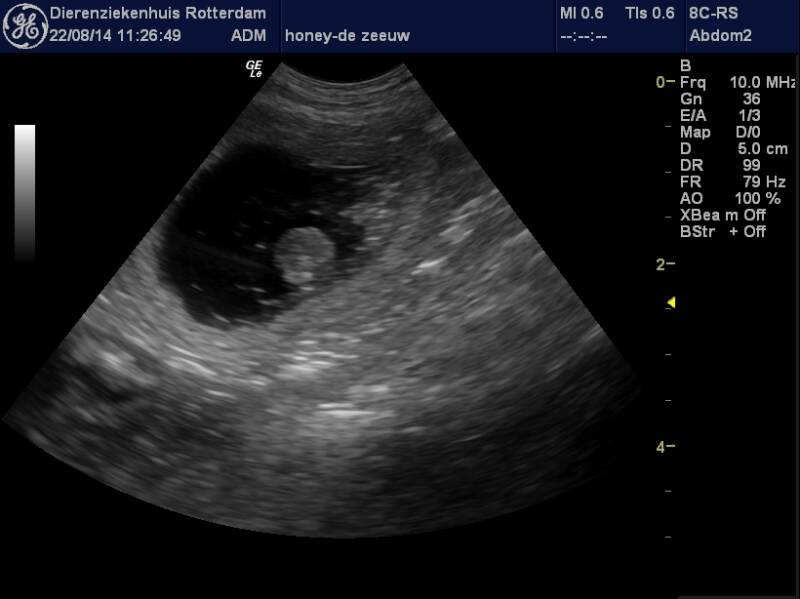

Als de hond ongeveer 25 dagen geleden gedekt is kan er een echo gemaakt worden.

Skeppsklockan's Honey was drachtig, inmiddels zijn de hondjes al lang volwassen die hier uit zijn gekomen.

Het teefje is van Jopie de Zeeuw-Boelee.